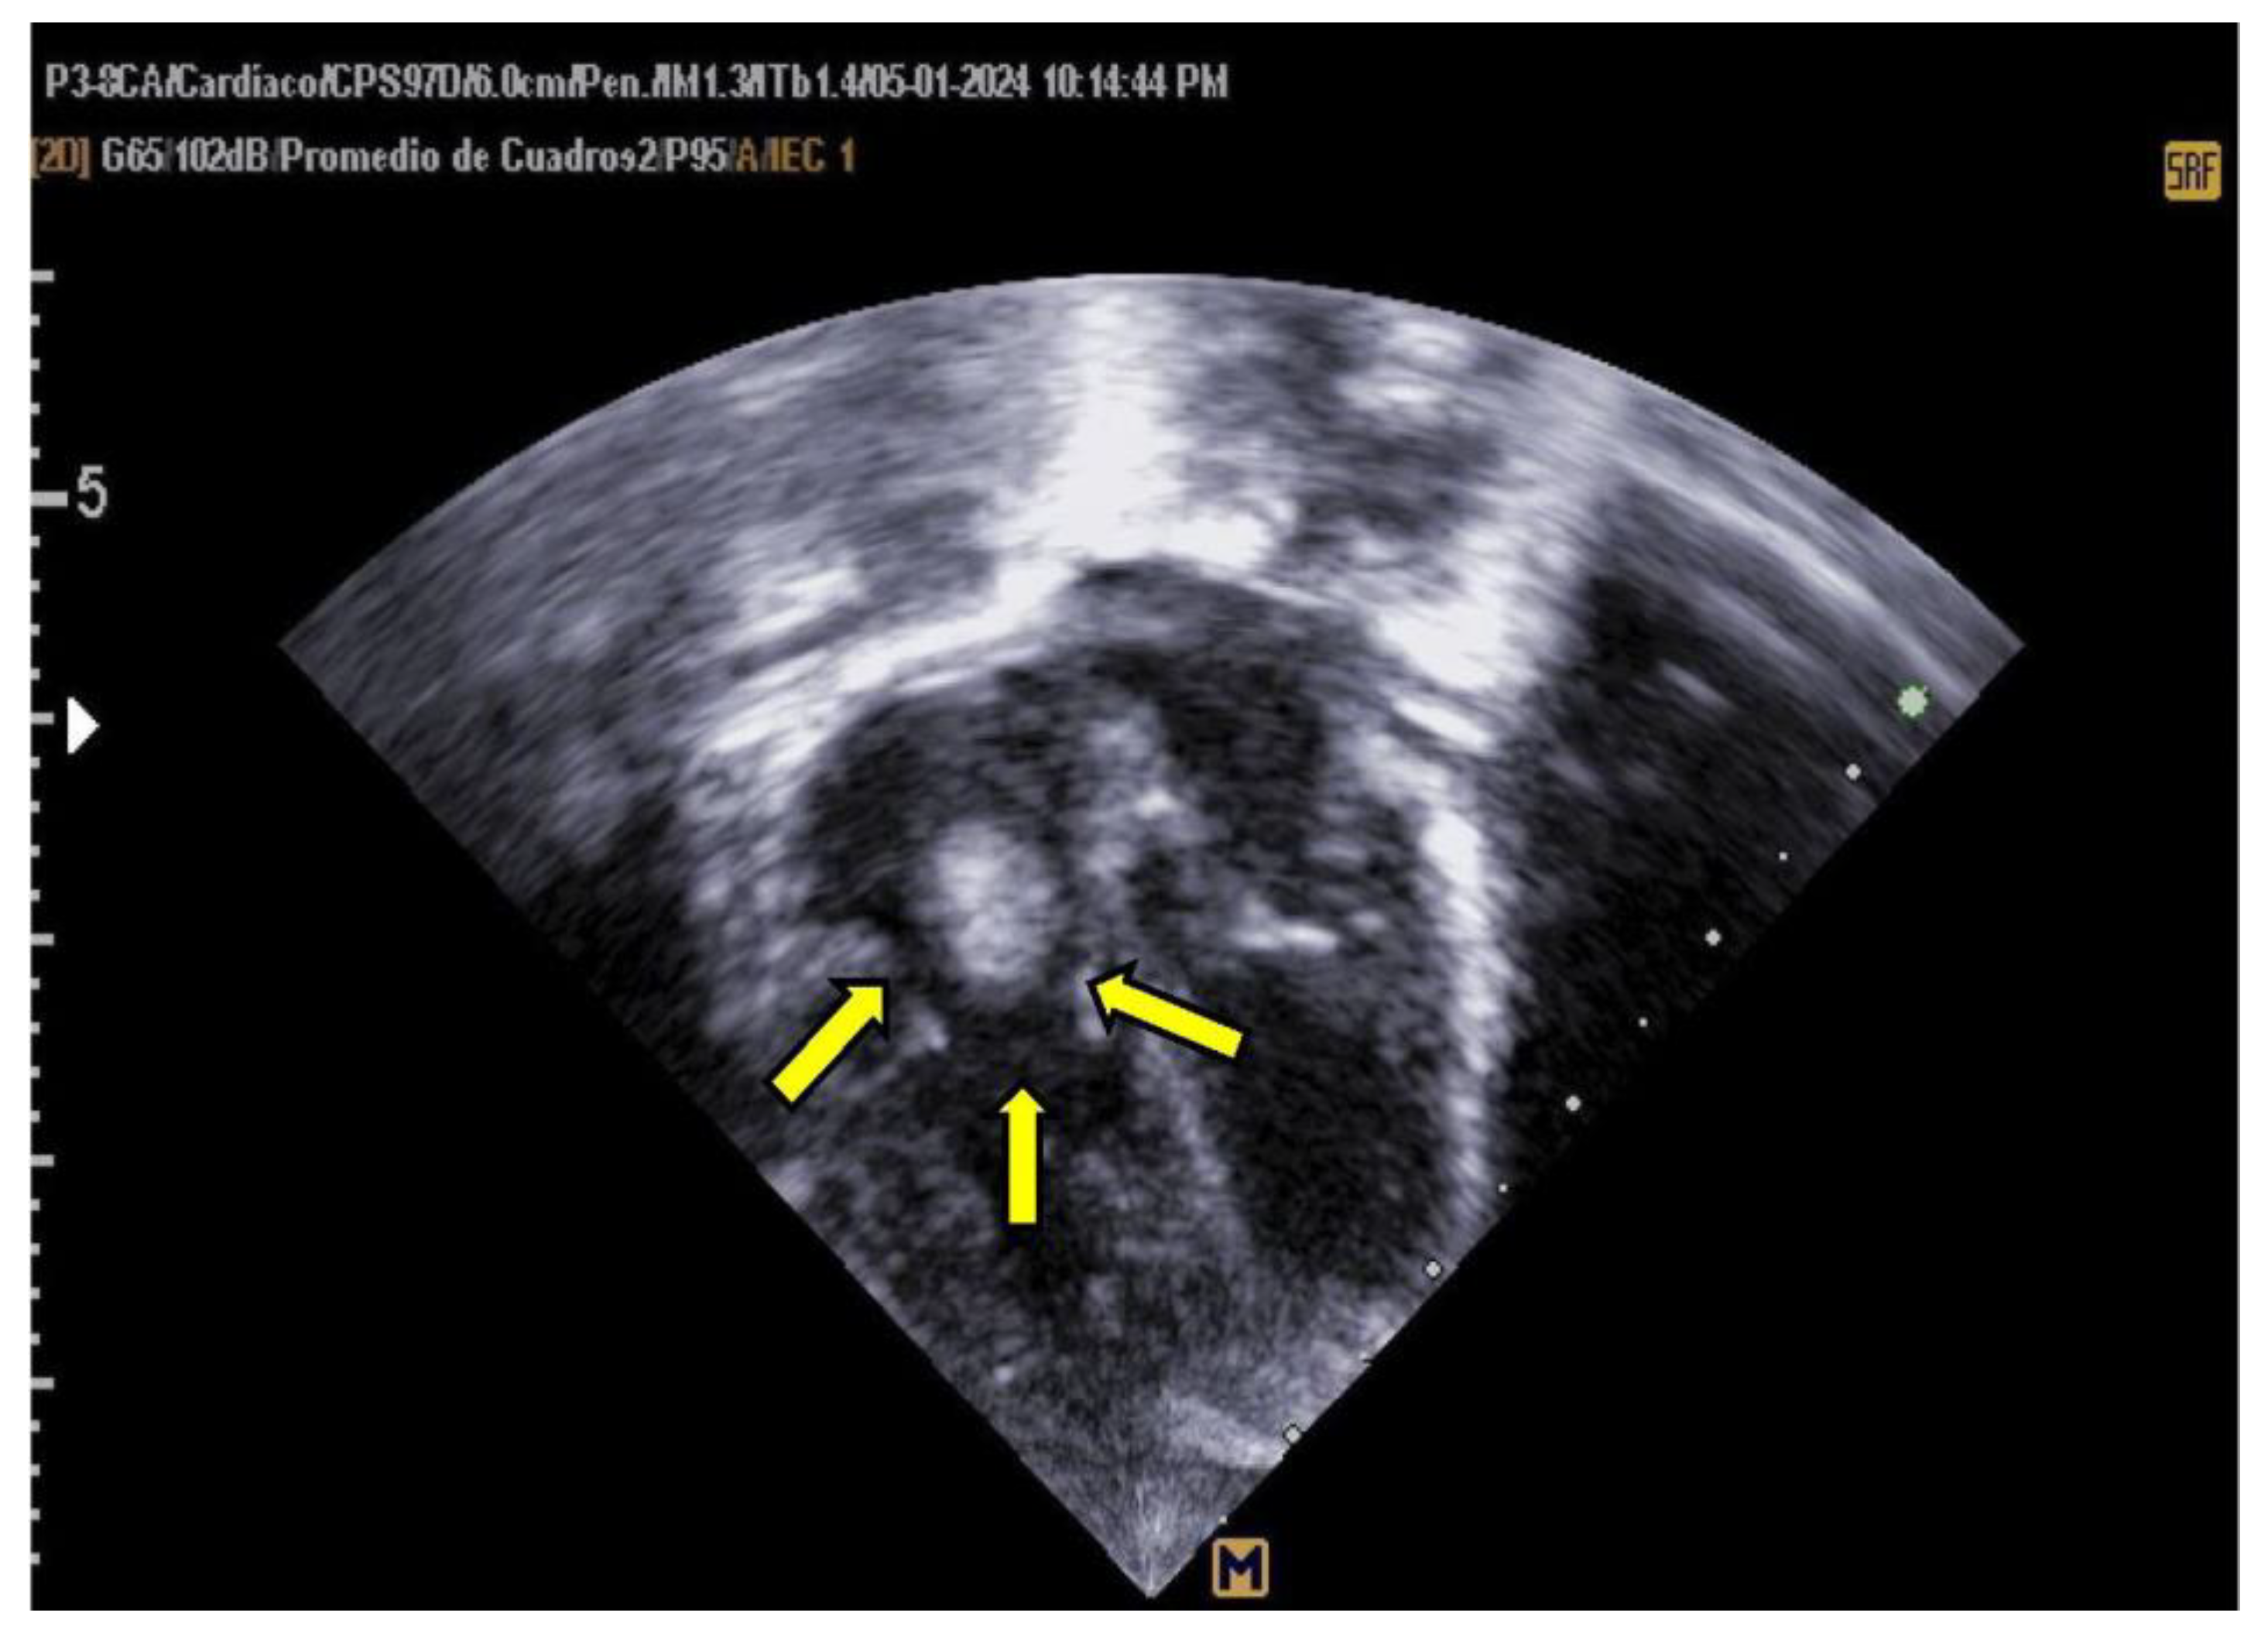

Empirical antimicrobial therapy with ampicillin and amikacin was initiated but later escalated to meropenem due to clinical signs of shock and poor response to initial treatment. Upon admission, a 4 Fr central venous catheter was placed in the left subclavian vein, with correct positioning verified by chest X-ray and adjusted by 1 cm. A pediatric cardiology consultation revealed a large thrombus measuring 1.5 × 0.7 cm in the right atrium, which was highly mobile and at risk of embolization, as shown in Figure 3 and 4.

Figure 3. Transthoracic Echocardiogram, Apical 4-Chamber View Shows a large thrombus measuring 1.5 x 0.7 cm is visible in the right atrium, pendulous and mobile during systole.

Figure 4. Transthoracic Echocardiogram, Apical 4-Chamber View The same thrombus measuring 1.5 x 0.7 cm is visible in the right atrium, pendulous and mobile, descending through the tricuspid valve into the right ventricle during diastole.